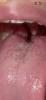

У ребенка и у мамы болит горло, хриплый голос, точки на языке

У мальчиков голос охрипший горло болит, так же у меня и болит горло щепит тоже , на языке какие то точки появились Фото а комы 😭 еще мелкая начинает болеть весело 😭

Кажется эти точки норм